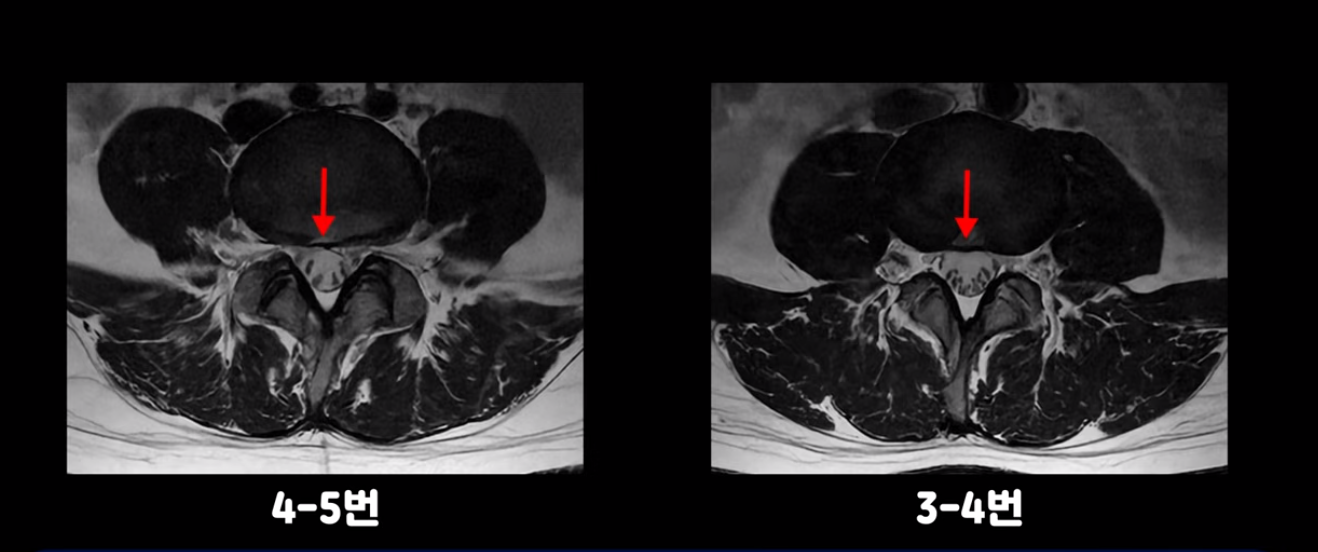

4번 5번과 3번 4번 마디도 디스크가 중앙으로 살짝 밀려나와있지만 최근에 섬유륜이 찢어진 것도 아니고, 신경 다발을 누를 정도로 심하게 밀려나와 있는 것도 전혀 아닙니다.

양쪽 신경 가지가 빠져나가는 추간공도 충분히 넓어서 신경학적 방사통을 일으킬 여지가 없습니다.

그럼 이 환자분의 양쪽 다리 저림과 발 저림 그리고 앉기만 하면 5분 내로 심한 허리 통증, 엉덩이 통증이 발생하는 원인은 뭘까요? 저희가 이런 디스크 내장증 얘기를 들으신 환자분들 치료 후기에서 수없이 설명하지만, 이런 증상이 디스크가 원인이 아닙니다. 이분도 여러 병원에서 증상과 MRI가 일치하지 않는다고 들으셨는데요.